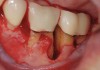

The workshop's group on periodontal soft-tissue root coverage procedures evaluated the predictability of root coverage procedures for single- and multiple-tooth Miller Class I and II10 periodontal recession defects. The workshop concluded that predictable root coverage was possible for Miller Class I and II recession involving a single tooth. When compared with the use of acellular dermal matrix graft (ADMG) (donor tissue) or EMD (porcine origin), procedures using a subepithelial connective tissue graft (SCTG) harvested from the patient's palate provided the best root coverage outcomes in conjunction with a coronally advanced flap.11 As alternatives to autogenous donor tissue, the workshop found strong evidence to support the use of an ADMG or EMD in conjunction with a coronally advanced flap and limited evidence to support the use of platelet-derived growth factor and xenogeneic collagen matrix.11 In addition, root coverage procedures were found to be effective for Miller Class I and II recession defects affecting multiple teeth, although the evidence is limited.11 Figure 1 and Figure 2 show the pretreatment and 1-year postoperative views of a soft-tissue root coverage treatment with SCTG and EMD that used a coronally advanced flap and a tunneling procedure. Figure 3 and Figure 4 depict the pretreatment and 3-year postoperative views of a root coverage procedure with ADMG and EMD that used a coronally advanced flap and a tunneling procedure (this patient was noncompliant following surgery and did not return to the office until the 3-year postoperative appointment).

(4.) Postoperative view after 3 years following treatment with ADMG and EMD using a coronally advanced flap and a tunneling procedure (the patient was noncompliant following surgery and did not return to the office until the 3-year postoperative appointment).

Figure 4